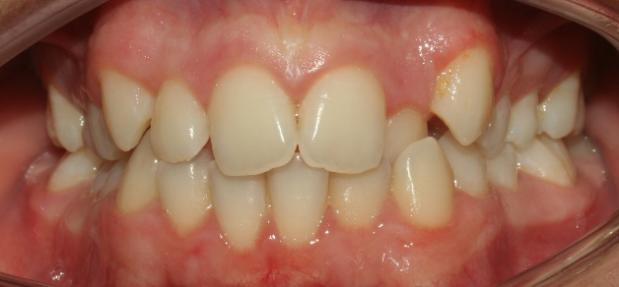

The patient in this case is a 15-year-old female who presented with mild third skeletal class with upper and lower tooth crowding at the beginning of the treatment. The whole process lasted for around 20 months employing traditional metal brackets.

Fig 1,2,3: the intraoral condition before orthodontics treatment & Fig 4,5,6: the intraoral condition after orthodontics treatment.